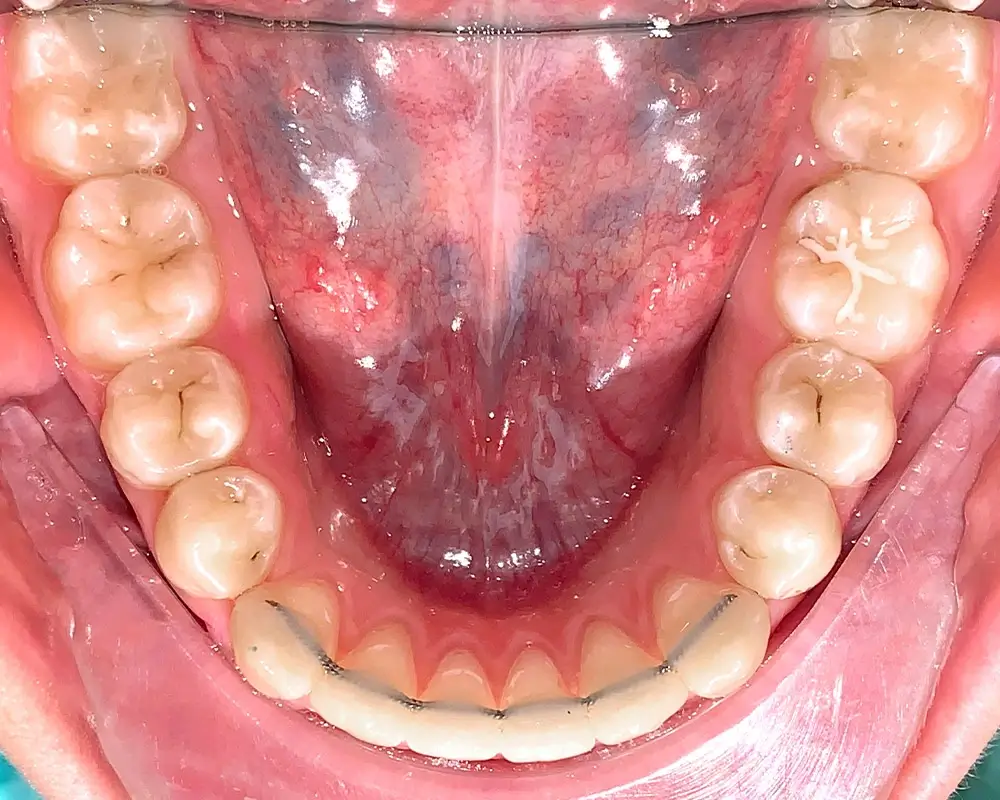

Скученность - Кейс 16

Эффективность устранения дефекта прикуса посредством элайнеров FlexiLigner.

Количество кап НЧ

20

Количество кап ВЧ

Результаты лечения